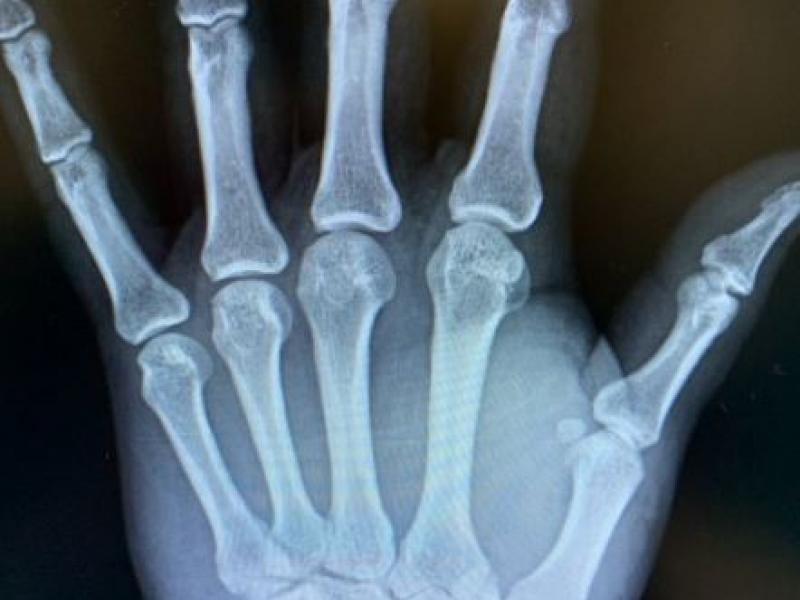

A 55 yo M presents to the ED w/ thumb pain following an MVC